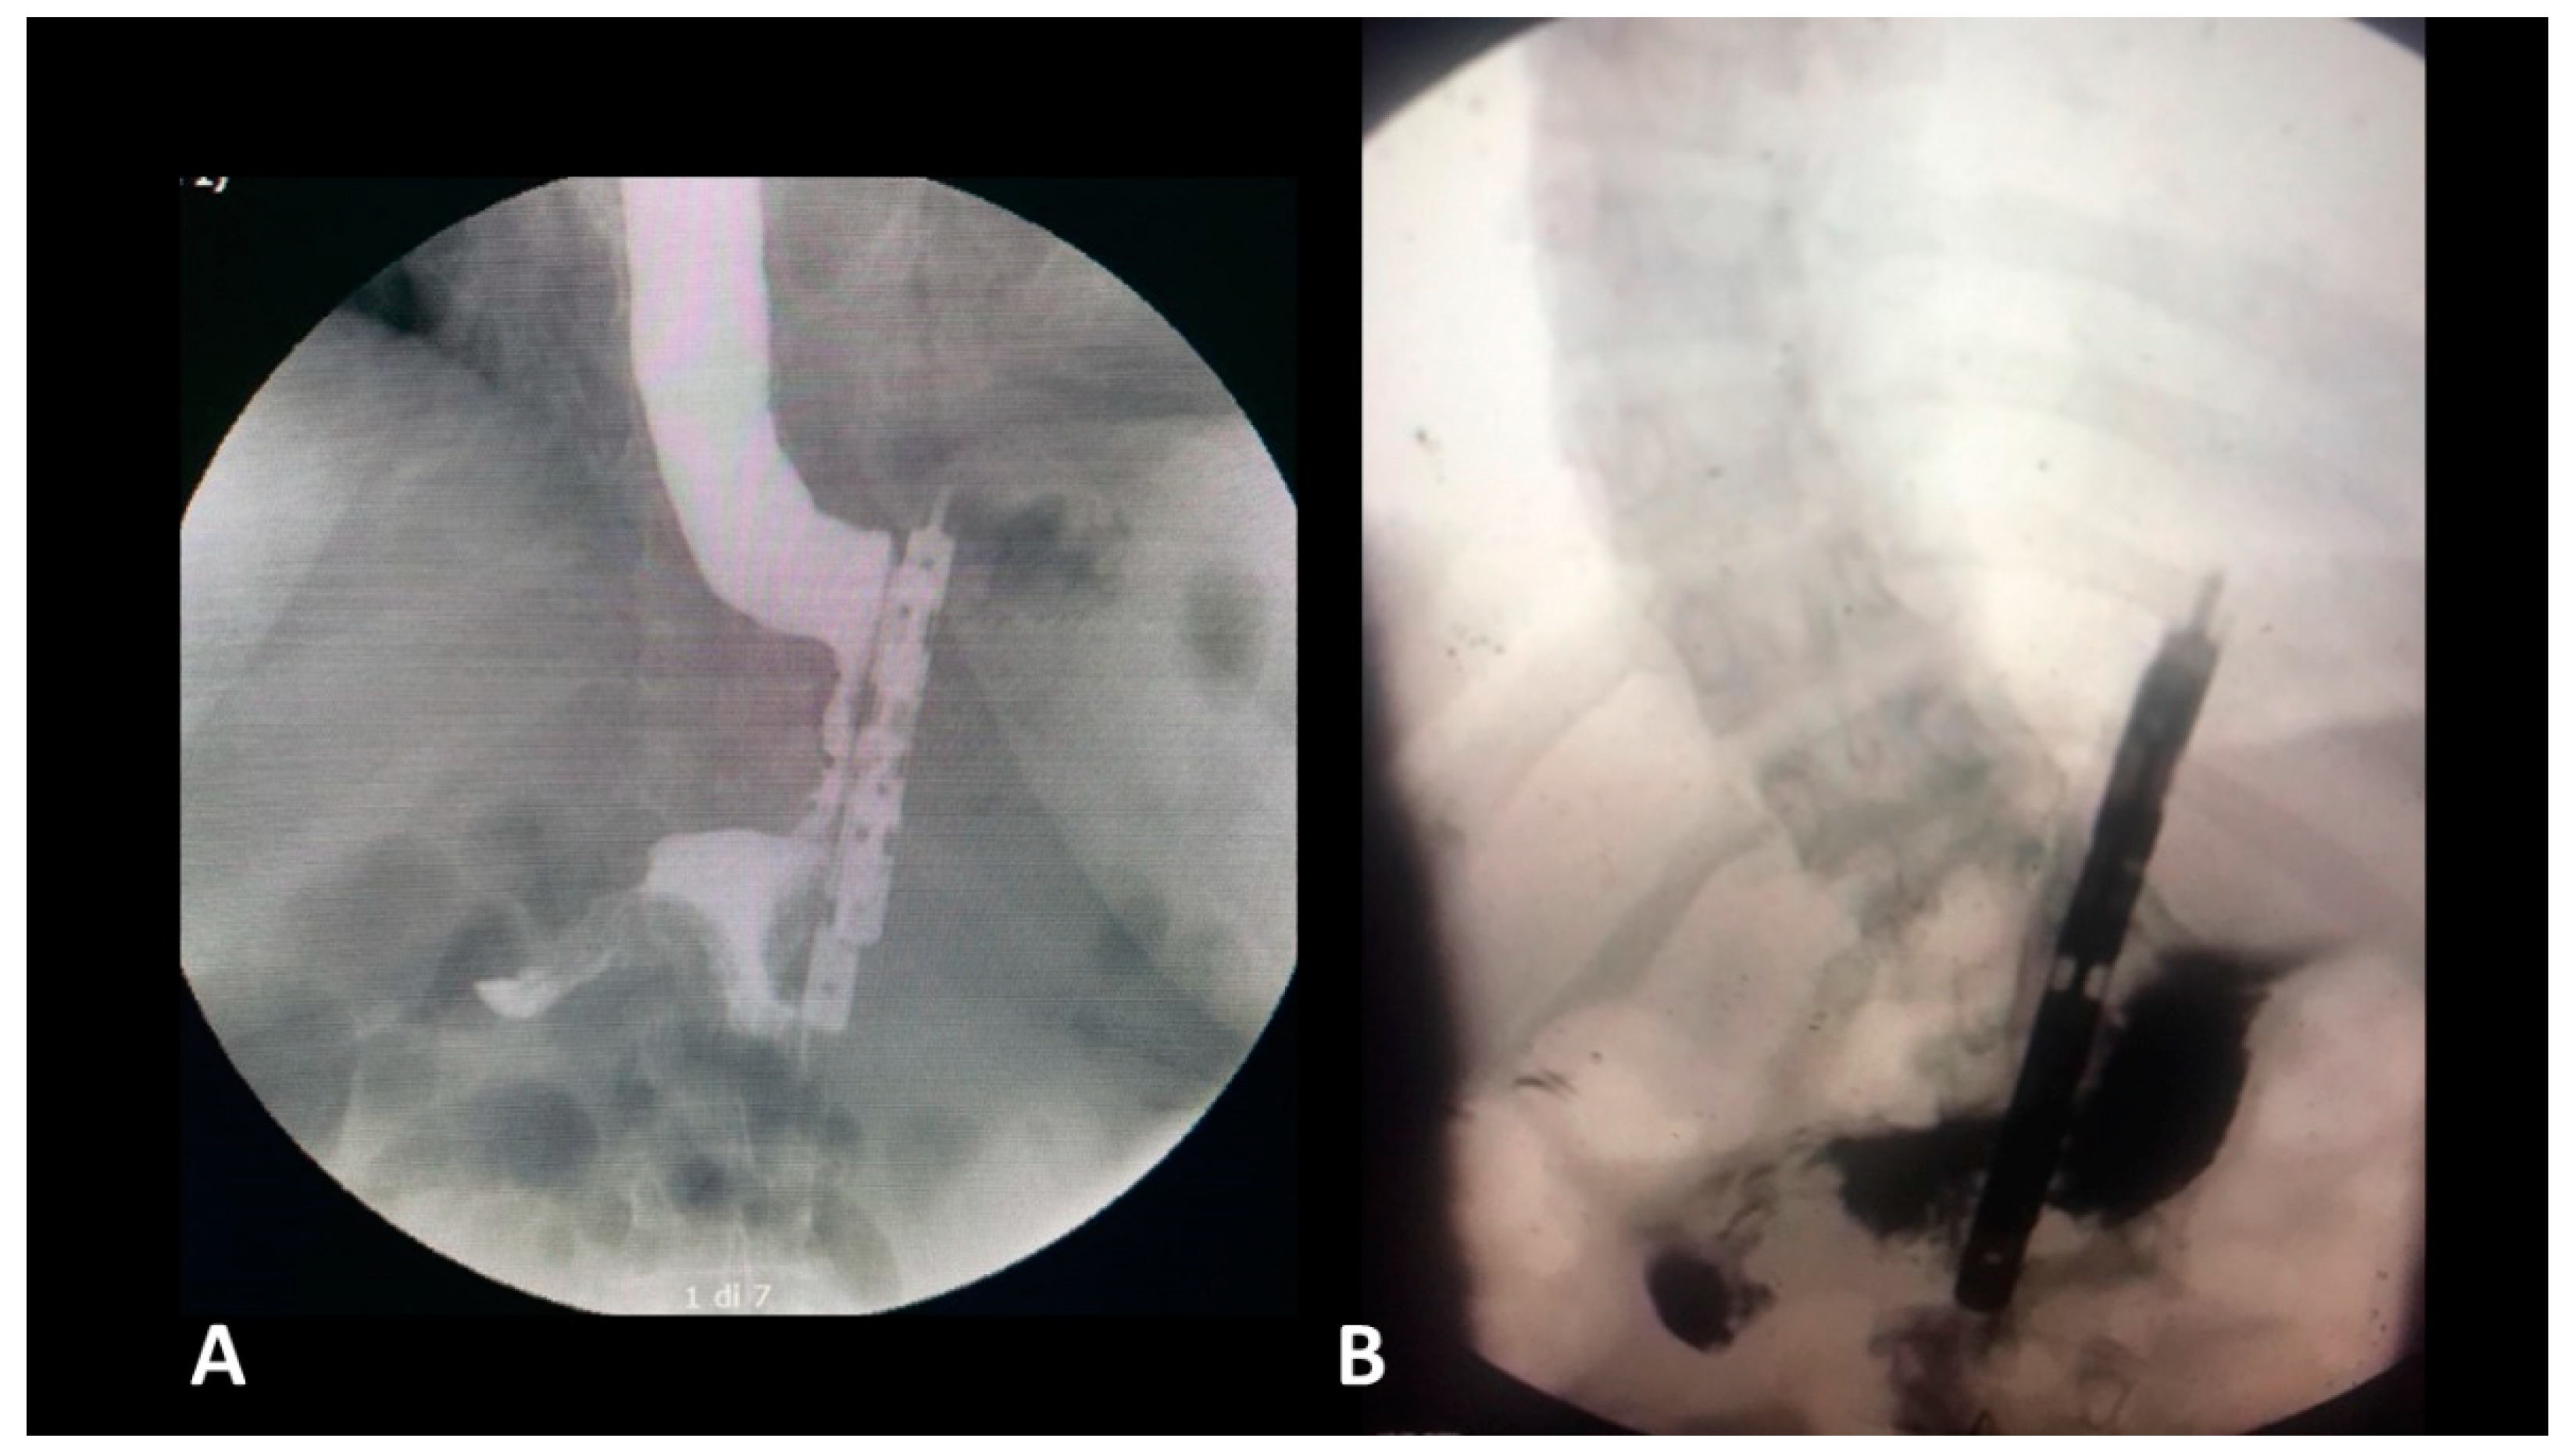

Figure 2.

Postoperative gastrografin swallow (A) no reflux; (B) with reflux in the gastric remnant.

- The presence of a distal opening at the bottom of the BariClip makes the procedure a low-pressure system. It balances the pressures with the excluded part of the stomach, thus allowing for a possible acid or bile reflux to go towards the fundus, to the excluded portion of the stomach and not the esophagus, like in the illustrated upper GI swallow (Figure 2).